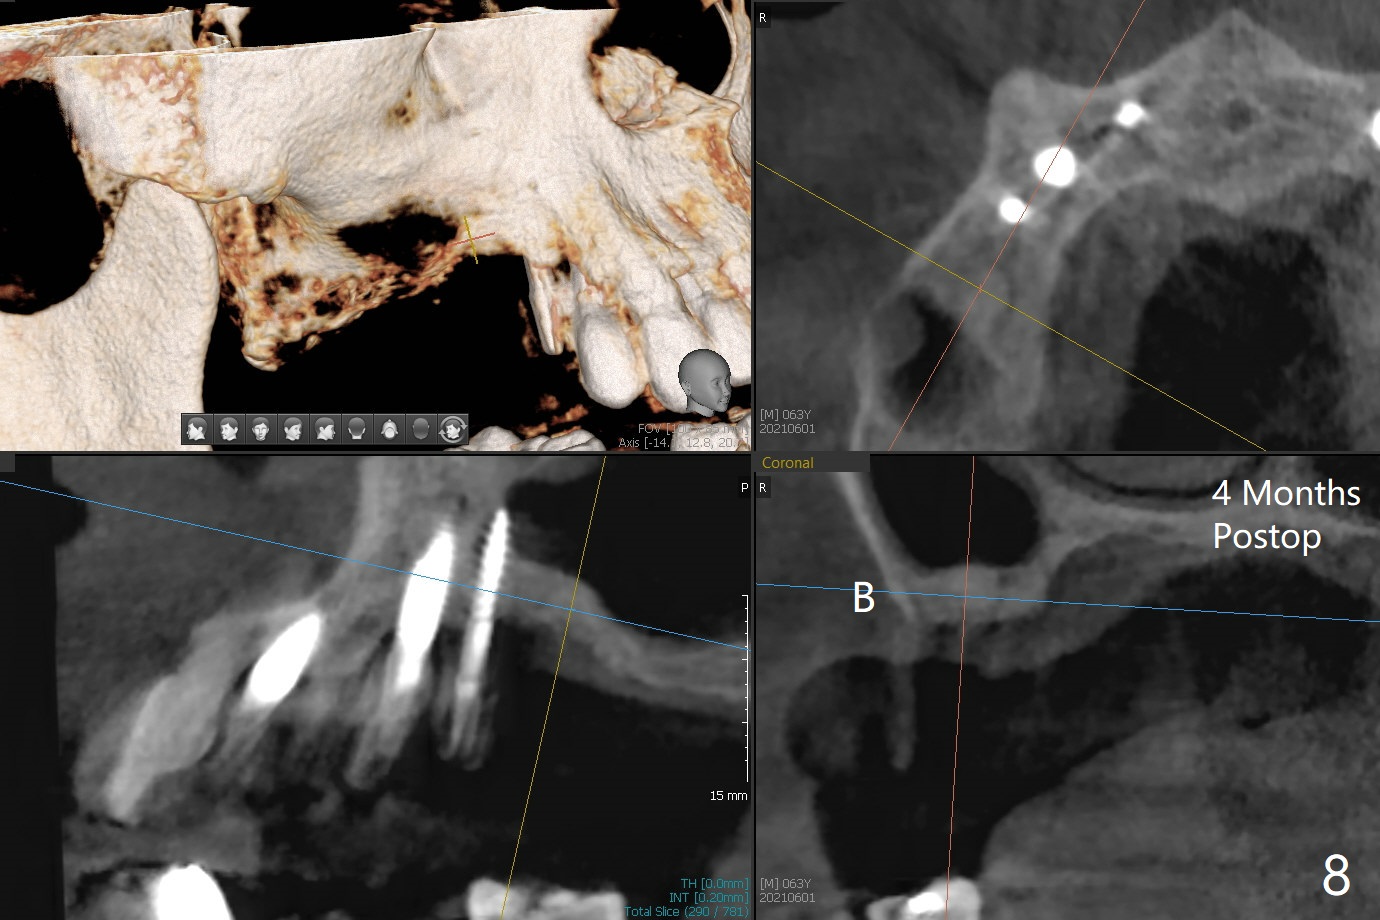

术前检查发现右上6颊侧牙龈沟有脓性分泌物(图一),翻瓣显示骨质吸收(图二),曾经植骨三次,只好去骨,取出植体,远中颊侧轻度上颌窦穿孔(图三:>),塞入小块PRF膜后,患处放置粘性骨粉,覆盖两块PRF膜和一片GEM Cap(9-12月吸收膜),三者近中一端有一个洞,挂在5基台上固定。术后即刻根尖片显示骨粉充填穿孔(图四:>),6缺失区以及5远中(*)。术后第二天牙周敷料脱落,术后16天病人回来,要求剪除缝线,伤口尚未关闭,下面黄色骨粉好像挺牢靠;为了减少继续骨粉丧失,使用树脂敷料(图五)。术后四周敷料稳定,牙龈健康,但是不放心下面伤口愈合,暂时没有撤去敷料。术后四个月骨质高度不足(图六至八),上颌窦膜薄,提升不容易,可放置5x7.3毫米植体(IBS),PRF。Return to No Caries 4 Placement 种植杂谈 Xin Wei, DDS, PhD, MS 1st edition 01/26/2021, last revision 07/30/2021